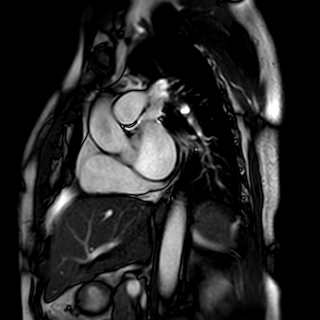

冠脉磁共振:给心脏和血管做 “全方位无创体检”

冠脉磁共振是利用磁场和无线电波成像的先进技术,无需插管、无电离辐射,既能清晰呈现冠状动脉的完整形态,又能同步评估心脏功能,相当于一次完成 “血管解剖 + 心肌功能” 的双重检查。

✅ 对血管:可精准识别冠状动脉主干及分支的狭窄程度、斑块性质(尤其是易破裂的危险斑块),还能发现先天性冠脉畸形、心肌桥等血管结构异常,就像给血管装了 “高清放大镜”,连血管壁的细微病变都无处遁形;

✅ 对心脏:能动态捕捉心脏跳动全过程,评估心肌缺血范围、梗死疤痕、心肌纤维化程度,还可精确计算心脏泵血功能,判断心肌肥厚、心脏扩大等结构问题,为心肌病、心肌炎等疾病诊断提供关键依据。